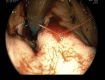

Background: Esophagogastric variceal bleeding (EGVB) is a potentially life-threatening complication of portal hypertension. Endoscopic treatment combined with pharmacotherapy remains the mainstay in the management of acute variceal bleeding.

Results: A total of 85 questionnaires were collected. There was no statistical difference in the selection of items (P < .05 indicated statistical significance). The majority of endoscopists (95.29%) offered EGV screening for patients with liver cirrhosis. The location, diameter, and risk factor classification was selected by 82.35% of endoscopists. Endoscopy + medication was preferred (42.35%) for the primary prophylaxis of moderate-to-severe EGVs. There was no statistical difference in emergency intervention time for active EGVB (P > .05). The response "patients receive emergency endoscopic intervention within 12 hours" was selected by 61.2% of the endoscopists. The preferred emergency treatment for EGVB was combination treatment (40%). Tissue adhesive embolization was selected for the treatment of gastric variceal bleeding by 74.12% of endoscopists; transjugular intrahepatic portosystemic stent shunt/percutaneous transhepatic variceal embolization were selected as remedial measures by 48.23% to 52.94% of endoscopists. In addition, 67.06% of endoscopists elected to perform secondary prophylaxis and treatment within 1 week after hemostasis. Endoscopy and endoscopy + medication were selected by 44.71% and 49.41% of endoscopists, respectively, for secondary prophylaxis. The choice of laboratory indicators did not differ with length of experience.